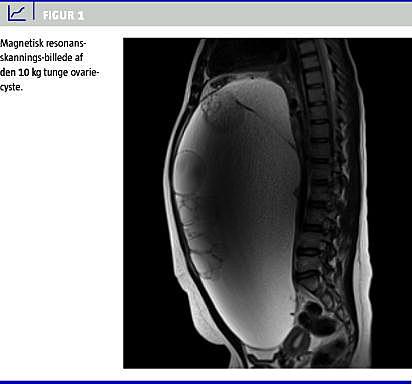

Blodprøver viste cancer antigen (CA)-125 på 39 kE/l, mens øvrige værdier var normale. En undersøgelse for plasma-humant choriongonadotropin var negativ. En ultralydskanning viste en stor intraabdominal multilobulær cystedannnelse. Supplerende magnetisk resonans-skanning viste en ovariecyste, der udgik fra venstre ovarie og målte 27 × 37 × 17 cm. Desuden fandt man højresidig hydronefrose forårsaget af kompression mod ureter.

Patienten blev efterfølgende opereret med laparotomi på et andet sygehus, hvor ovariecysten inklusive hele venstre ovarie og salpinx blev fjernet fuldstændigt i et stykke med en vægt 10,3 kg (Figur 1 ). Der blev i øvrigt fundet normale makroskopiske forhold intraabdominalt uden tegn til spredning eller indvækst.